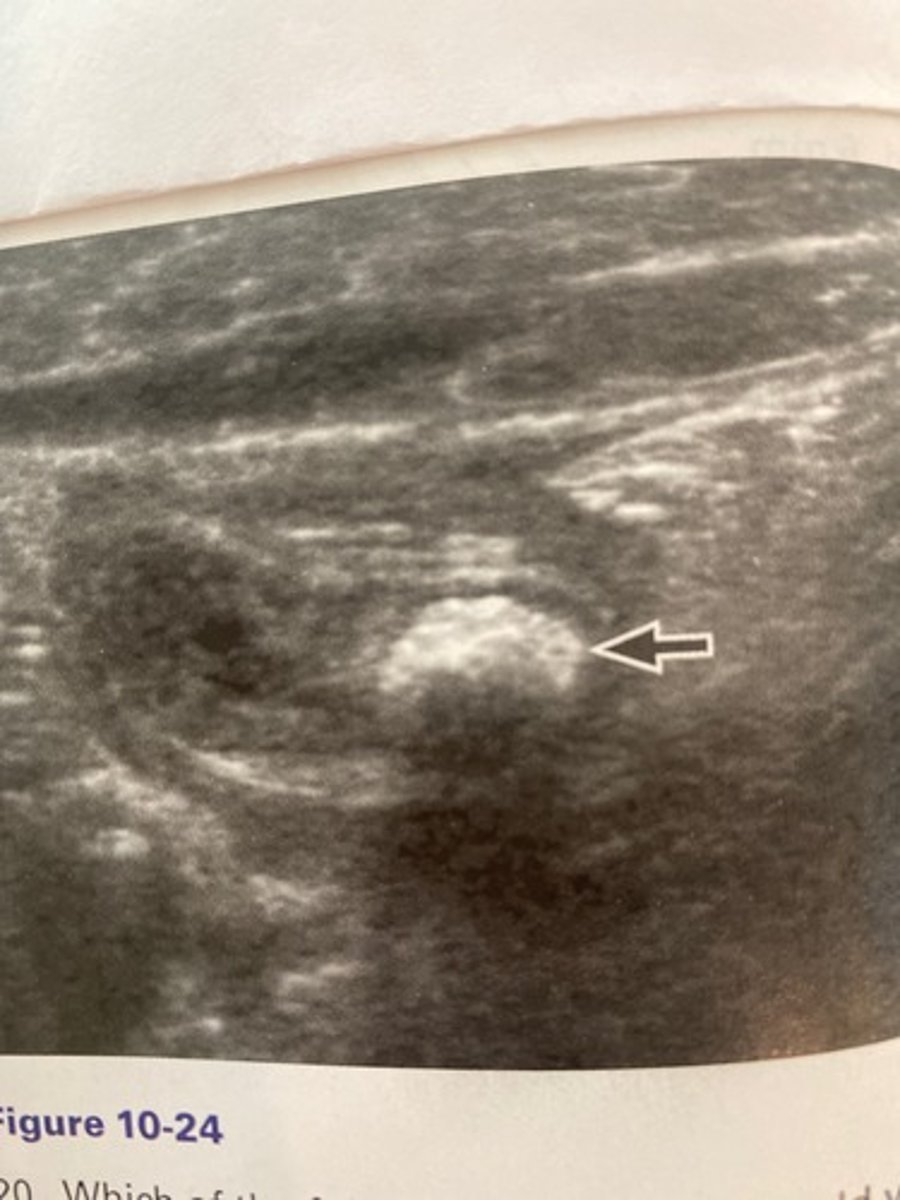

a. Appendicolith

What does the arrow demonstrate in the patien in Figure 10-24 who complained of focal right lower quadrant pain?

b. Thyroid in the belly

c. Olive sign

d. McBurney sign